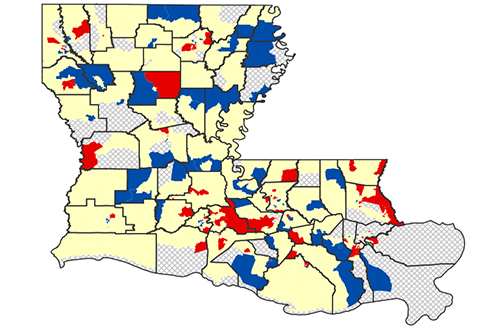

LSU Health New Orleans Releases Latest Report on Cancer in Louisiana

The Louisiana Tumor Registry at LSU Health New Orleans School of Public Health has published Cancer in Louisiana Volume 38. It includes information on cancer incidence and deaths between 2016 and 2020, incidence and mortality trends from 1988 to 2020, survival statistics for cases diagnosed from 2009 to 2019, and followed into 2020, and prevalence of cancer cases diagnosed from January 1, 2000, to January 1, 2020. More

LSU Health New Orleans Research Quantifies Effect of Chronic Diseases on Racial Disparity in COVID-Associated Hospitalizations

LSU Health New Orleans conducted the first research using disease surveillance data to quantify the effect of chronic diseases on racial disparity in COVID-associated hospitalizations. The research team, led by Xiao-Cheng Wu, MD, MPH, Professor and Director of the Louisiana Tumor Registry at LSU Health New Orleans School of Public Health, reports that chronic diseases explained almost two-fifths of the racial disparity in COVID-associated hospitalizations among cancer patients, specifically common chronic diseases such as hypertension, diabetes and chronic kidney disease. More

LSU Health New Orleans LA Tumor Registry Releases 6th Census Tract Cancer Incidence Report

LSU Health New Orleans Louisiana Tumor Registry (LTR) has published the sixth report of statewide cancer incidence rates by census tract. The publication, which reports 2010-2019 combined cancer incidence data, found that 81% of the census tracts in Louisiana met publication criteria for all cancers combined. More

LSU Health’s LA Tumor Registry Publishes Latest Statewide Cancer Incidence, Mortality & Survival Info

LSU Health New Orleans’ Louisiana Tumor Registry has published the latest volume in its annual Cancer in Louisiana monograph series. Cancer in Louisiana, Volume 37, 2015 – 2019, documents cancer incidence and mortality from 2015 to 2019 in Louisiana, as well as incidence and mortality trends from 1988 to 2019. It also includes survival statistics for cases diagnosed from 2008 to 2018 and followed into 2019, as well as prevalence for cancer cases diagnosed from January 1, 2000, to January 1, 2019. More

LSU Health New Orleans LA Tumor Registry Releases 5th Census Tract Cancer Incidence Report

LSU Health New Orleans Louisiana Tumor Registry (LTR) has published the fifth report of statewide cancer incidence rates by census tract. The publication, which reports 2009-2018 combined cancer incidence data, found that 81% of the census tracts in Louisiana met publication criteria for all cancers combined. For specific cancer types, fewer census tracts met the criteria. For the Louisiana census tracts meeting the criteria, the incidence rates for all cancers combined and for specific cancer types were compared with the corresponding rates for the entire state. More

Latest Cancer in LA Volume Contains New Incidence & Mortality Tables for Industrial Corridor

LSU Health New Orleans School of Public Health’s Louisiana Tumor Registry has published the latest report on cancer incidence and mortality in Louisiana – Cancer in Louisiana 2014-2018 (Volume 36). More